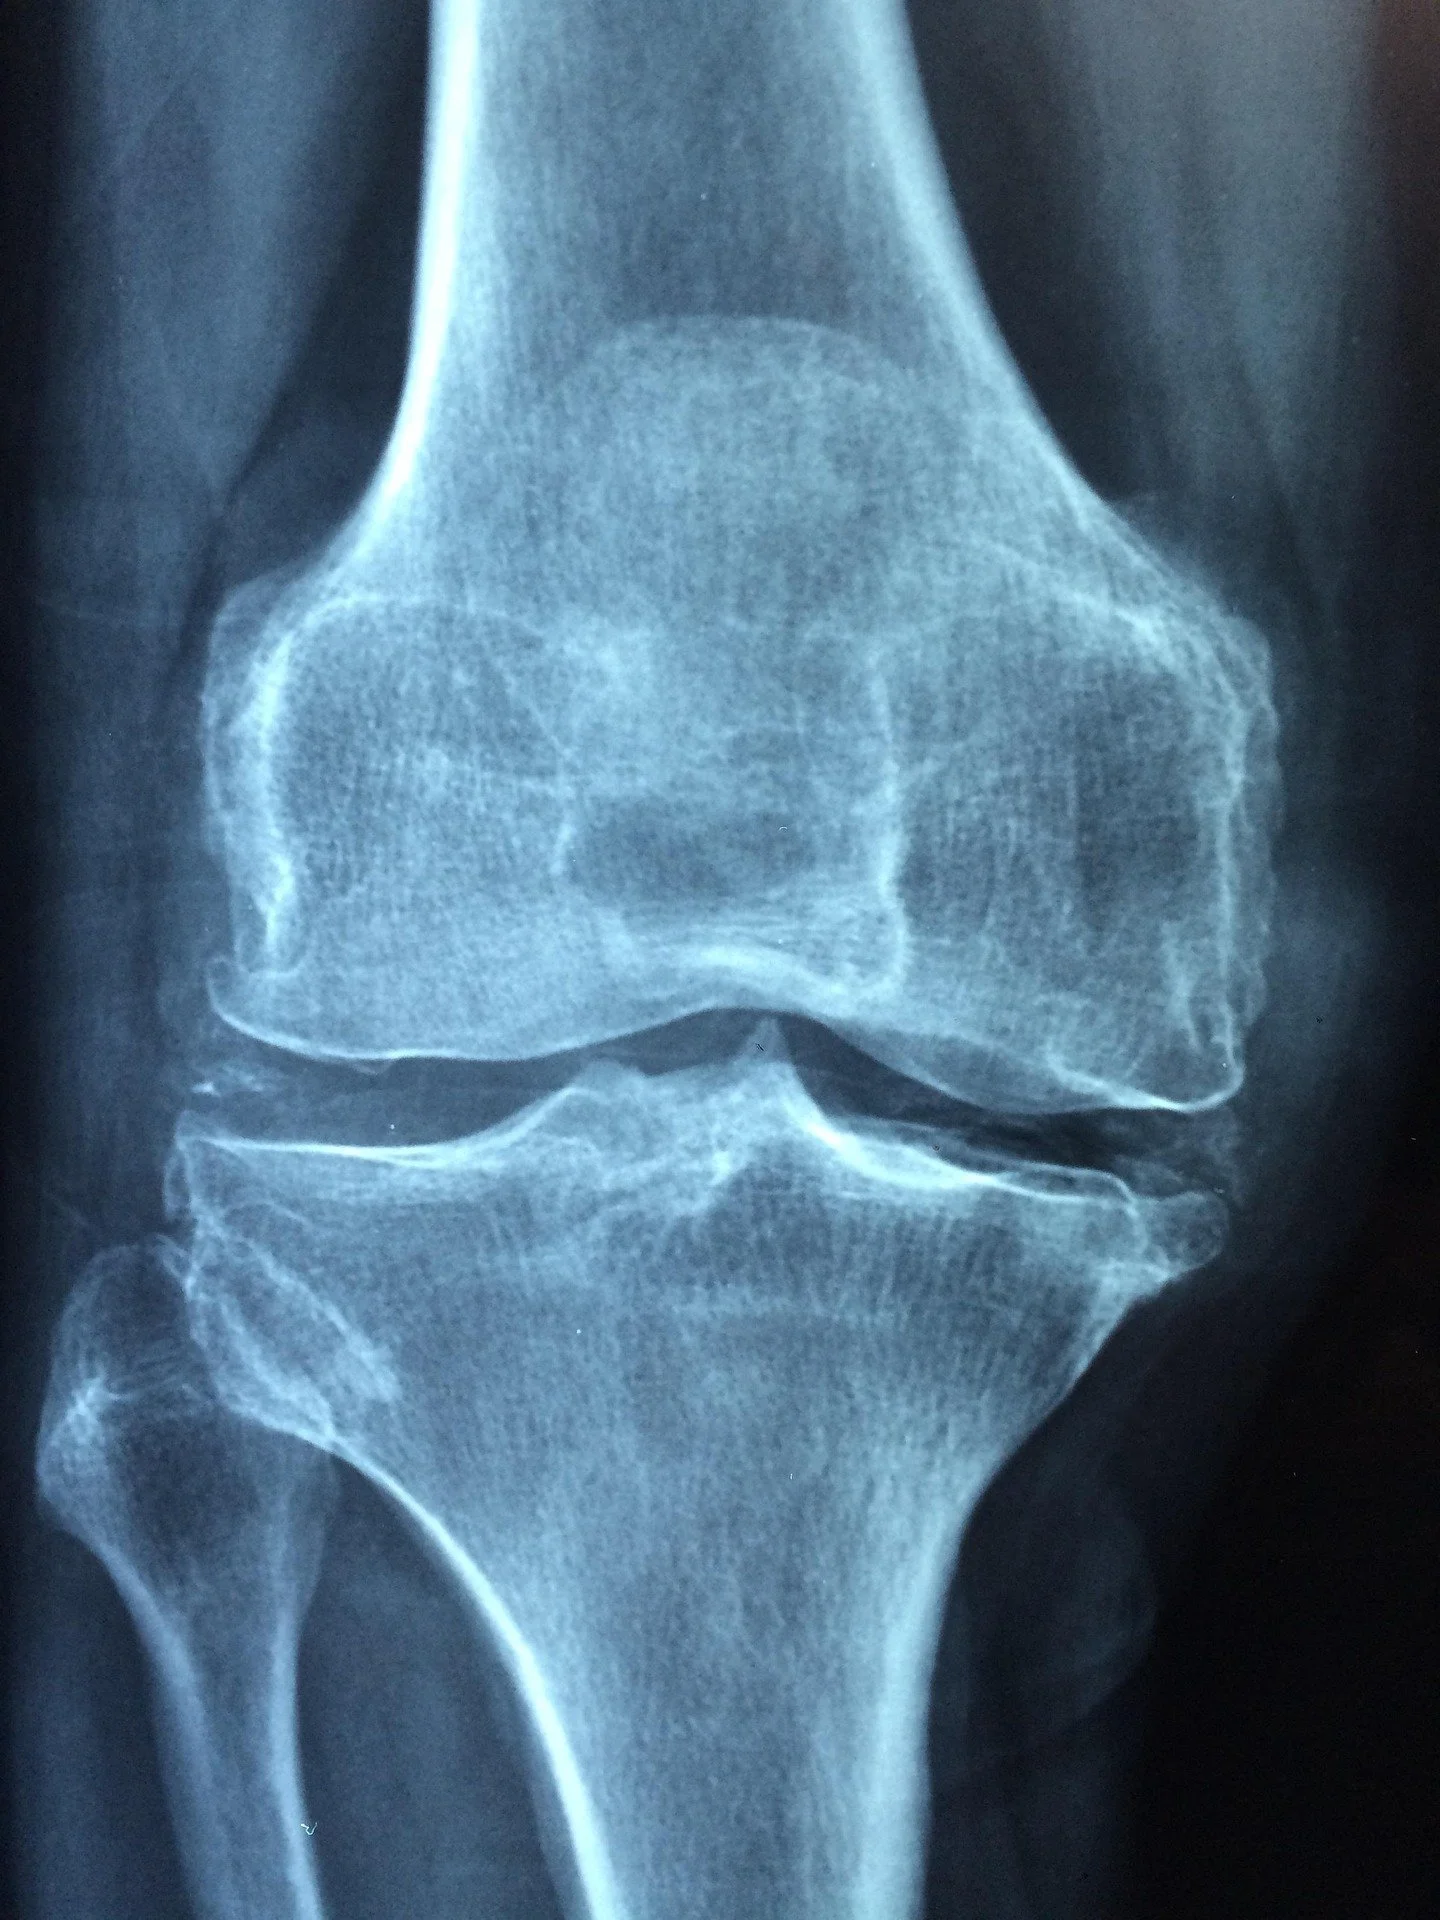

Osteoarthritis (OA) is a condition that can affect any joint in the body. A joint is a junction point where two bones meet. These bones are covered with a layer of cartilage that acts like a smooth protective surface or “bumper”.

When osteoarthritis occurs, this cartilage has begun to wear away or thin progressively. This can lead to pain, as the nerves within the bones are more exposed to the forces applied through the joints.